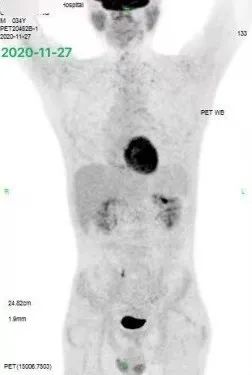

诊断明确后,患者立即开始接受化疗,前三个疗程采用了 R-CHOPE 为主的化疗,考虑到患者中枢神经系统受累及风险较高,中间加入了高剂量甲氨蝶呤 1 疗程进行中枢防控,同时还联合了来那度胺等靶向药物治疗,3 疗程后患者症状缓解,PET-CT 评估达到了部分缓解。进而患者继续接受了 3 疗程 R-CHOPE 及高剂量甲氨蝶呤的化疗。

不幸的是,患者的疗效并没有进一步提高,反而在上述治疗后的 PET 评估中出现了疾病进展,如下图 2: